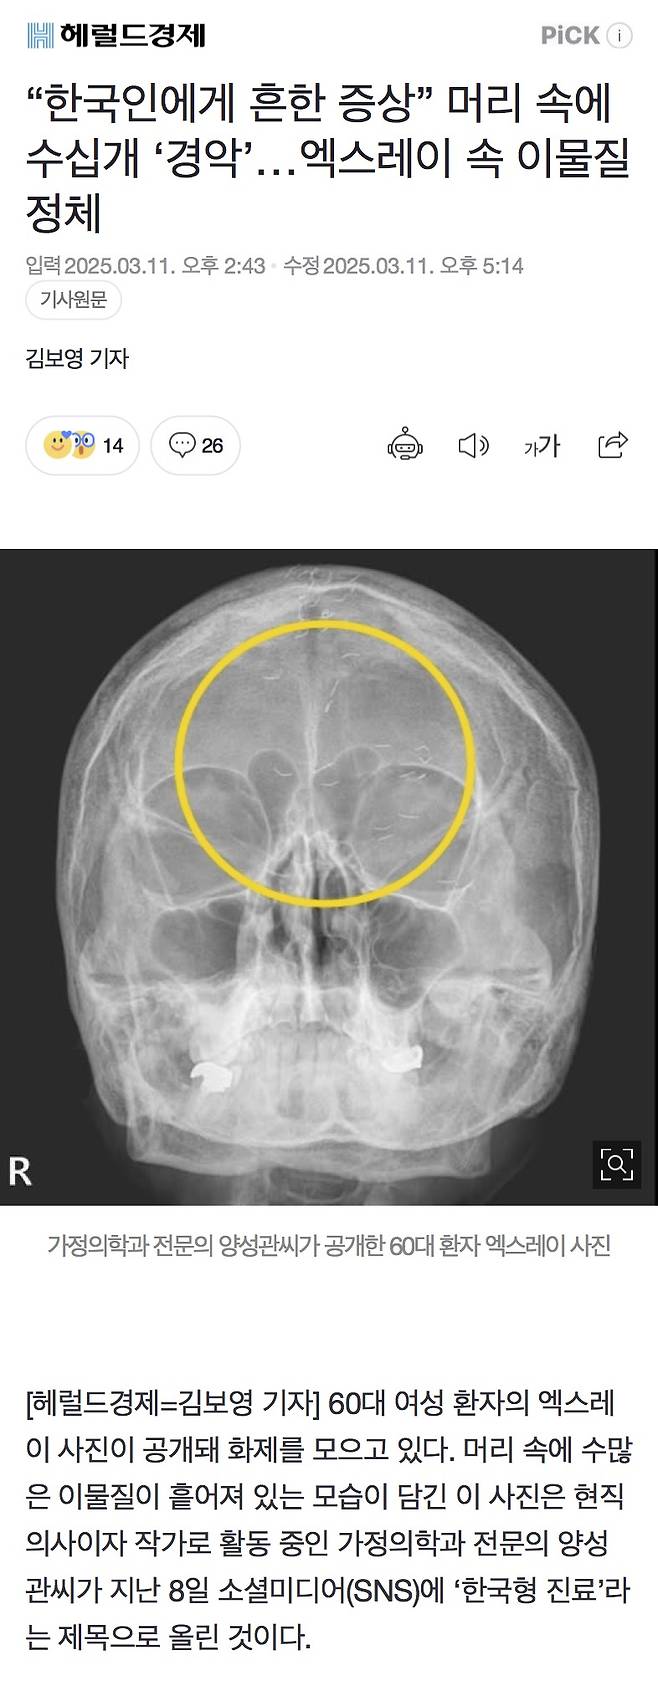

물론 요즘은 미용도 유행해서 얼굴에도 박음

문제는 이것들이 금이라 안녹아서

해외에서는 경악을 한다고 함

해외 학술지에도 올라간 금실 박힌 엑스레이 사진